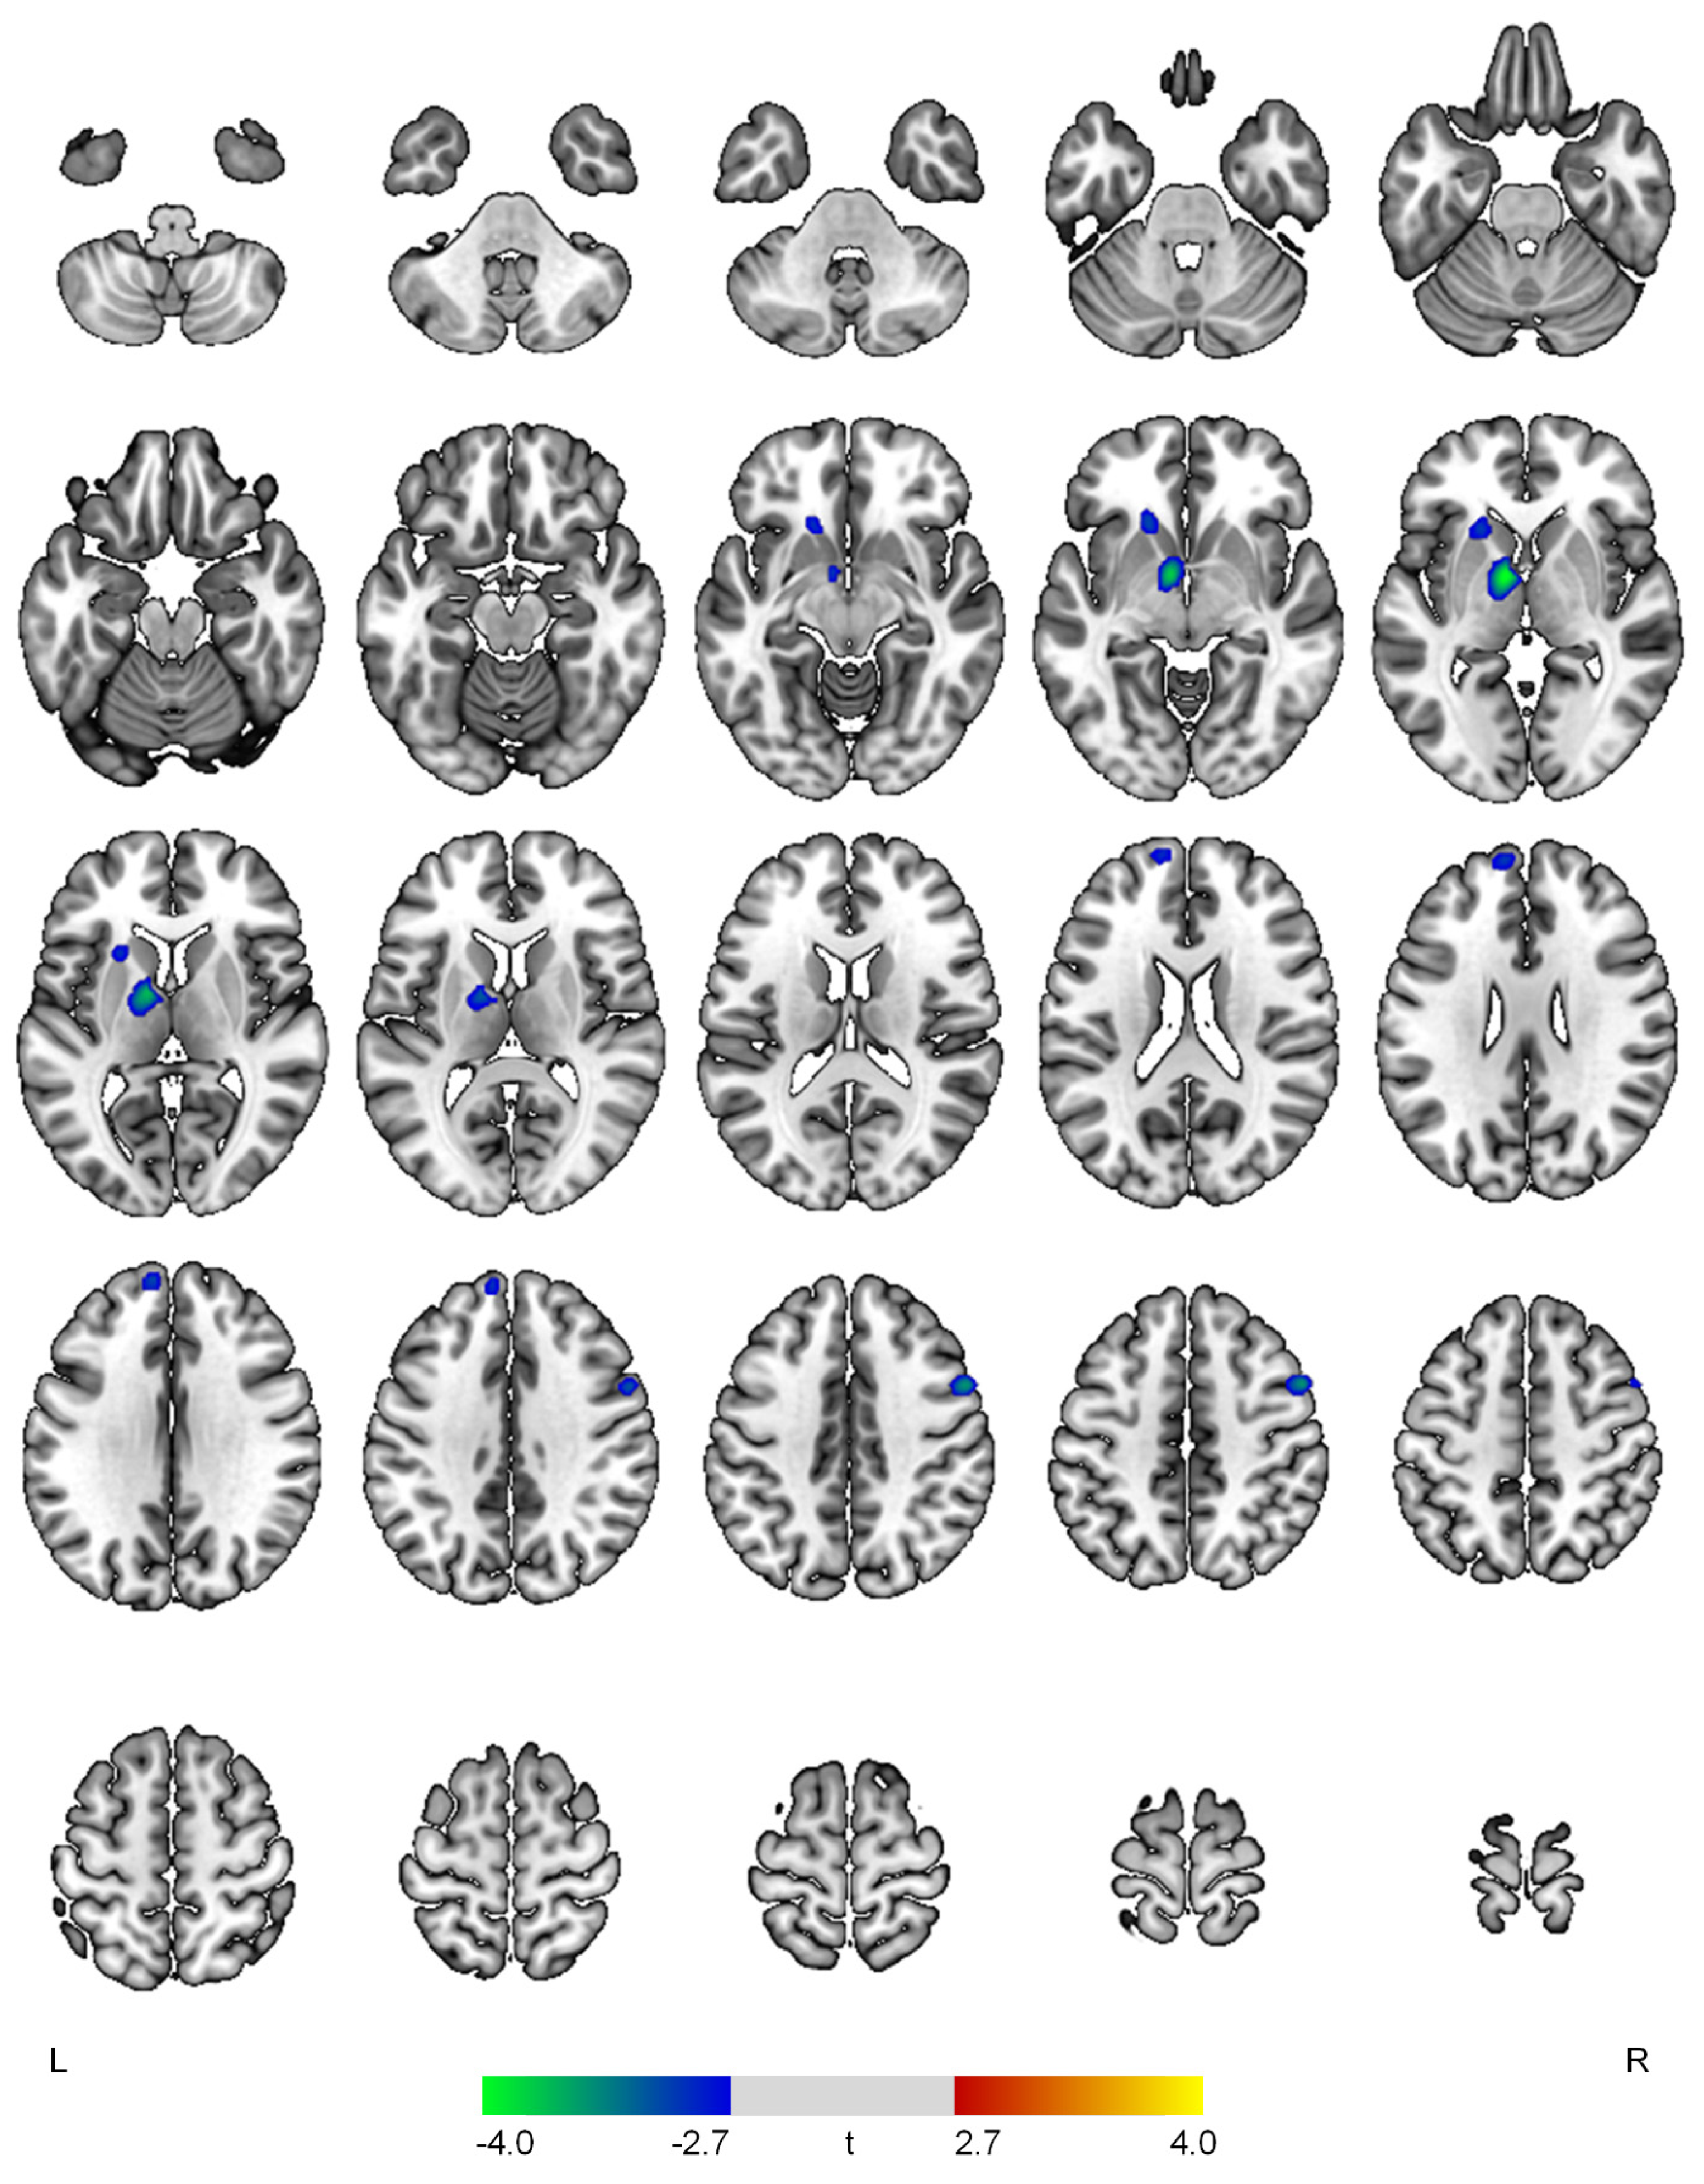

| Negative correlations with the affective domain | ||||

| L thalamus | 4.08 | <0.001 | 427 | −8, −2, −2 |

| R precentral gyrus | 3.59 | <0.001 | 172 | 54, 8, 42 |

| L superior frontal gyrus | 3.06 | 0.002 | 160 | −8, 56, 30 |

| L caudate | 3.05 | 0.002 | 165 | −18, 22, −4 |